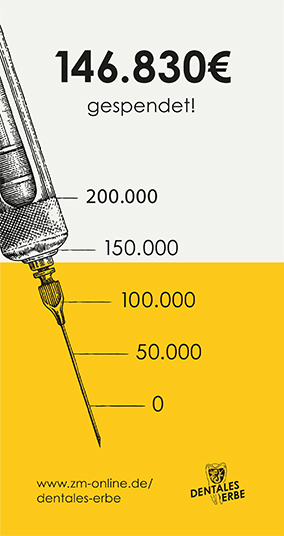

Pulpotomie nach traumatischer Kronen-Wurzel-Fraktur

Nach Abtastung der Schädelbasis sowie der Trigeminusdruckpunkte ergab sich kein Anhalt für eine Schädelverletzung. Extraoral zeigten sich eine Schwellung und eine Rötung der Ober- und der Unterlippe. Intraoral zeigte sich eine Kronenfraktur an Zahn 11 (Abbildung 1a), die Pulpa war exponiert und es lag eine Sulkusblutung palatinal vor (Abbildung 1b). Auf Kälte reagierten die Zähne 13—23 sensibel. Die Perkussion an Zahn 11 war stark positiv, die Sondierungstiefen palatinal waren physiologisch.

Eine Alveolarfortsatzfraktur konnte nach Abtastung ausgeschlossen werden. Auf dem Ausgangsröntgenbild zeigten sich an 11 eine koronale Transluzenz, die bis zur Pulpakammer extendiert war, sowie ein leicht transluzenter Spalt auf Höhe des mittleren Wurzeldrittels (Abbildung 2). Eine Wurzelquerfraktur an 11 konnte daher angenommen werden. Die Dislokation der beiden Fragmente betrug röntgenologisch weniger als ein Millimeter.